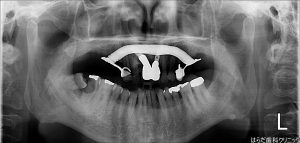

本日右上4,5,6番のインプラント埋入手術が行われました。

こちらのレントゲン写真では左上になります。

この患者様はインプラントを入れるには骨の高さが足りなかったので、サイナスリフトという骨を足す手術も行いました。

骨を足す手術には主にソケットリフトとサイナスリフトがあるのですが、今回の患者様はサイナスリフトでした。